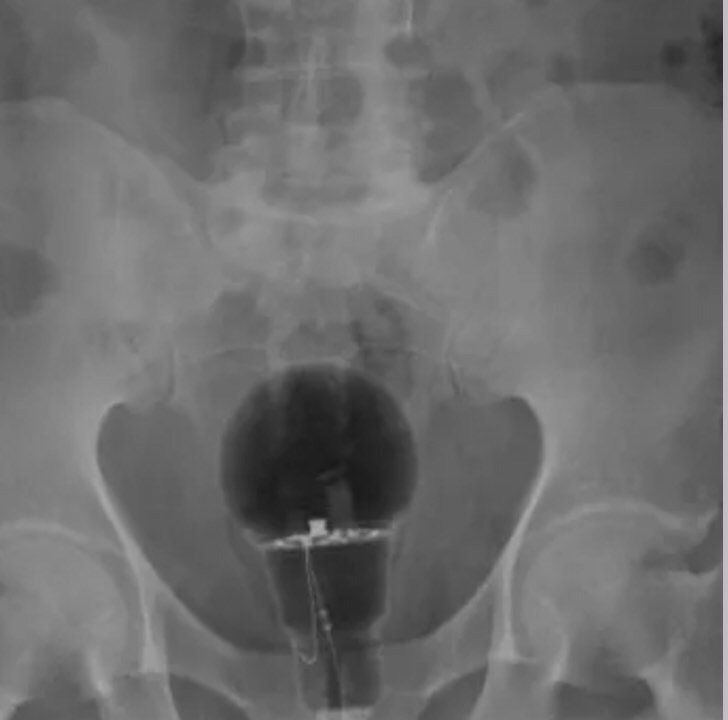

Après une idée lumineuse, un homme de 53 ans s'est rendu à l'hôpital à cause de douleurs localisées dans son anus. Lors de l'examen physique et du toucher rectal, les médecins n'ont rien vu, c'est grâce à une radiographie, qu'ils ont pu remarquer qu'une ampoule était coincée dans les fesses de cet homme.

De nos jours, les gens font preuve de beaucoup d'imagination, des aliments (Concombre) des verres, des accessoires de cuisine et autres jouets sexuels sont souvent utilisés par certaines personnes pour prendre du plaisir sexuel. Cependant, le patient de 53 ans, n'a pas donné d'informations concernant la présence de cet objet à cet endroit. «On ne savait pas non plus comment l'ampoule avait été insérée ou si l'individu avait subi des dommages à long terme», souligne le Daily Mail.